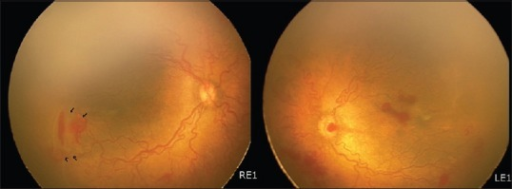

Plus disease: 후극부 혈관의 확장(dilatation) + 사행(tortuosity) — 활성 질환의 지표

A-ROP (Aggressive ROP): 후극부에 빠르게 진행하는 심한 형태 (과거 AP-ROP)

- 간접검안경 검사: 산동 후 scleral depression 하에 시행 (표준)

- RetCam (wide-field imaging): 기록/원격 판독에 유용